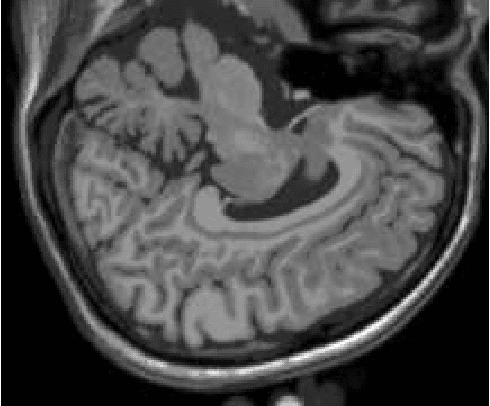

The materialist dialectical method is a philosophical investigative method to analyze aspects of reality. These aspects are viewed as complex processes composed by basic units named poles, which interact with each other. Dialectics has experienced considerable progress in the 19th century, with Hegel's dialectics and, in the 20th century, with the works of Marx, Engels, and Gramsci, in Philosophy and Economics. The movement of poles through their contradictions is viewed as a dynamic process with intertwined phases of evolution and revolutionary crisis. In order to build a computational process based on dialectics, the interaction between poles can be modeled using fuzzy membership functions. Based on this assumption, we introduce the Objective Dialectical Classifier (ODC), a non-supervised map for classification based on materialist dialectics and designed as an extension of fuzzy c-means classifier. As a case study, we used ODC to classify 181 magnetic resonance synthetic multispectral images composed by proton density, $T_1$- and $T_2$-weighted synthetic brain images. Comparing ODC to k-means, fuzzy c-means, and Kohonen's self-organized maps, concerning with image fidelity indexes as estimatives of quantization distortion, we proved that ODC can reach almost the same quantization performance as optimal non-supervised classifiers like Kohonen's self-organized maps.